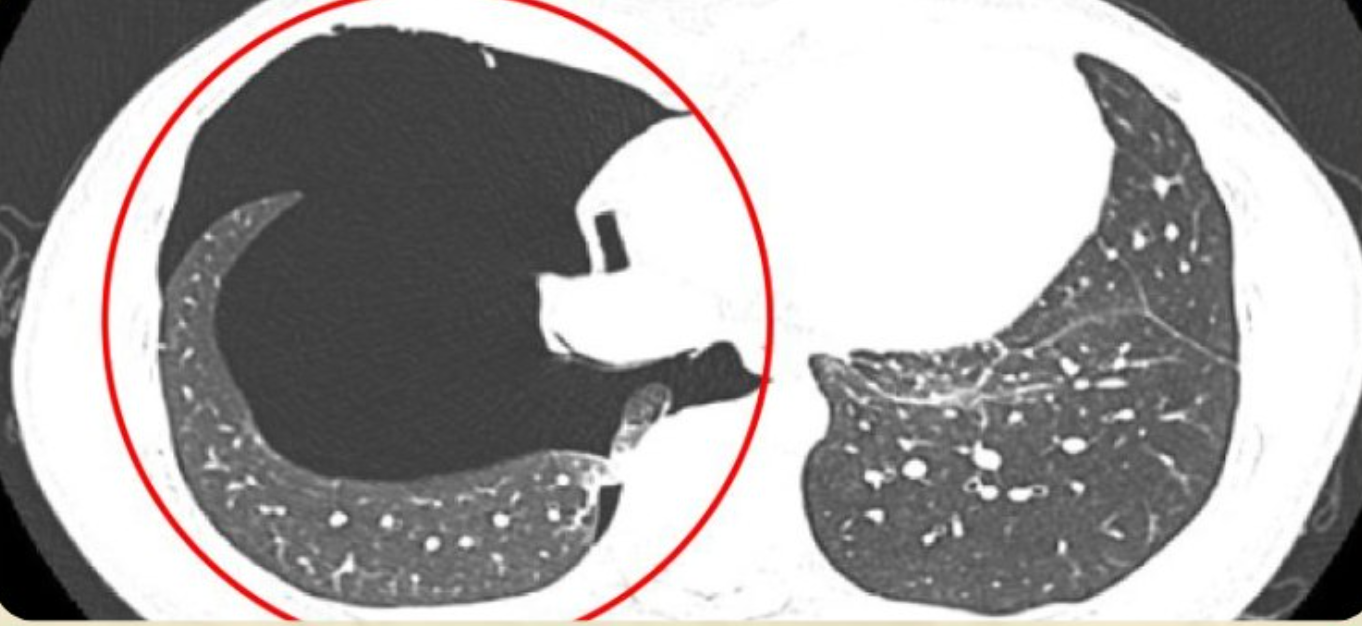

Kết quả chụp X-quang và CT ngực ghi nhận hình ảnh tràn khí khoang màng phổi phải kèm theo tổn thương nhu mô phổi (đám đông đặc ở thùy trên và phân thùy S5 phổi phải). Bác sĩ nhận định tình trạng này do chấn thương phổi trong lúc gắng sức.

Bác sĩ khuyến cáo người bệnh cần nhận diện sớm triệu chứng như đau ngực đột ngột, khó thở khi gắng sức, sau đó nhanh chóng đến cơ sở y tế để được chẩn đoán, can thiệp kịp thời. Trong quá trình điều trị, chụp cắt lớp vi tính (CT scan) lồng ngực đóng vai trò quan trọng giúp chẩn đoán chính xác và đánh giá mức độ tổn thương trong các trường hợp tràn khí màng phổi.

So với phương pháp chụp X-quang ngực thông thường, với khả năng dựng hình cắt lớp theo nhiều mặt phẳng, CT scan có độ nhạy cao hơn, giúp phát hiện những lượng khí nhỏ không rõ trên phim X-quang, đồng thời cung cấp hình ảnh chi tiết về nhu mô phổi và khoang màng phổi.

Từ đó, bác sĩ có thể xác định chính xác vị trí và mức độ tràn khí, phát hiện các nguyên nhân tiềm ẩn như bóng khí, kén khí dưới màng phổi. Ngoài ra, kỹ thuật này còn giúp đánh giá các tổn thương phối hợp như dập phổi, tụ khí dưới da, tràn khí trung thất… hỗ trợ lựa chọn phương án điều trị phù hợp, từ theo dõi bảo tồn đến can thiệp dẫn lưu, hoặc phẫu thuật.